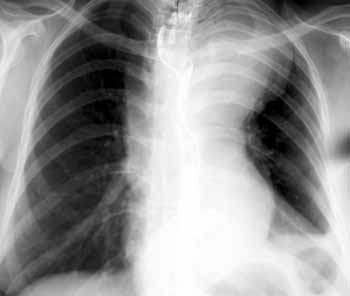

Синдром Марфана.

Рис. 4. Аневризма дуги и нисходящего отдела аорты. При УЗИ брюшной полости выявлено распространение расслоения на брюшную аорту.